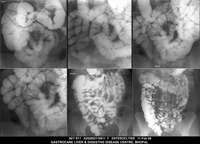

Section: ENTEROCLYSIS

Total: 205 Cases